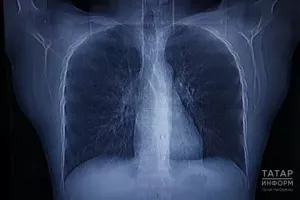

Туберкулезга каршы – бергәләп!

24 мартта Бөтендөнья туберкулезга каршы көрәш көне билгеләп үтелә. Иң куркынычлардан саналучы авыру дөньяда үлемгә китерүче 10 төп сәбәпнең берсе булып тора